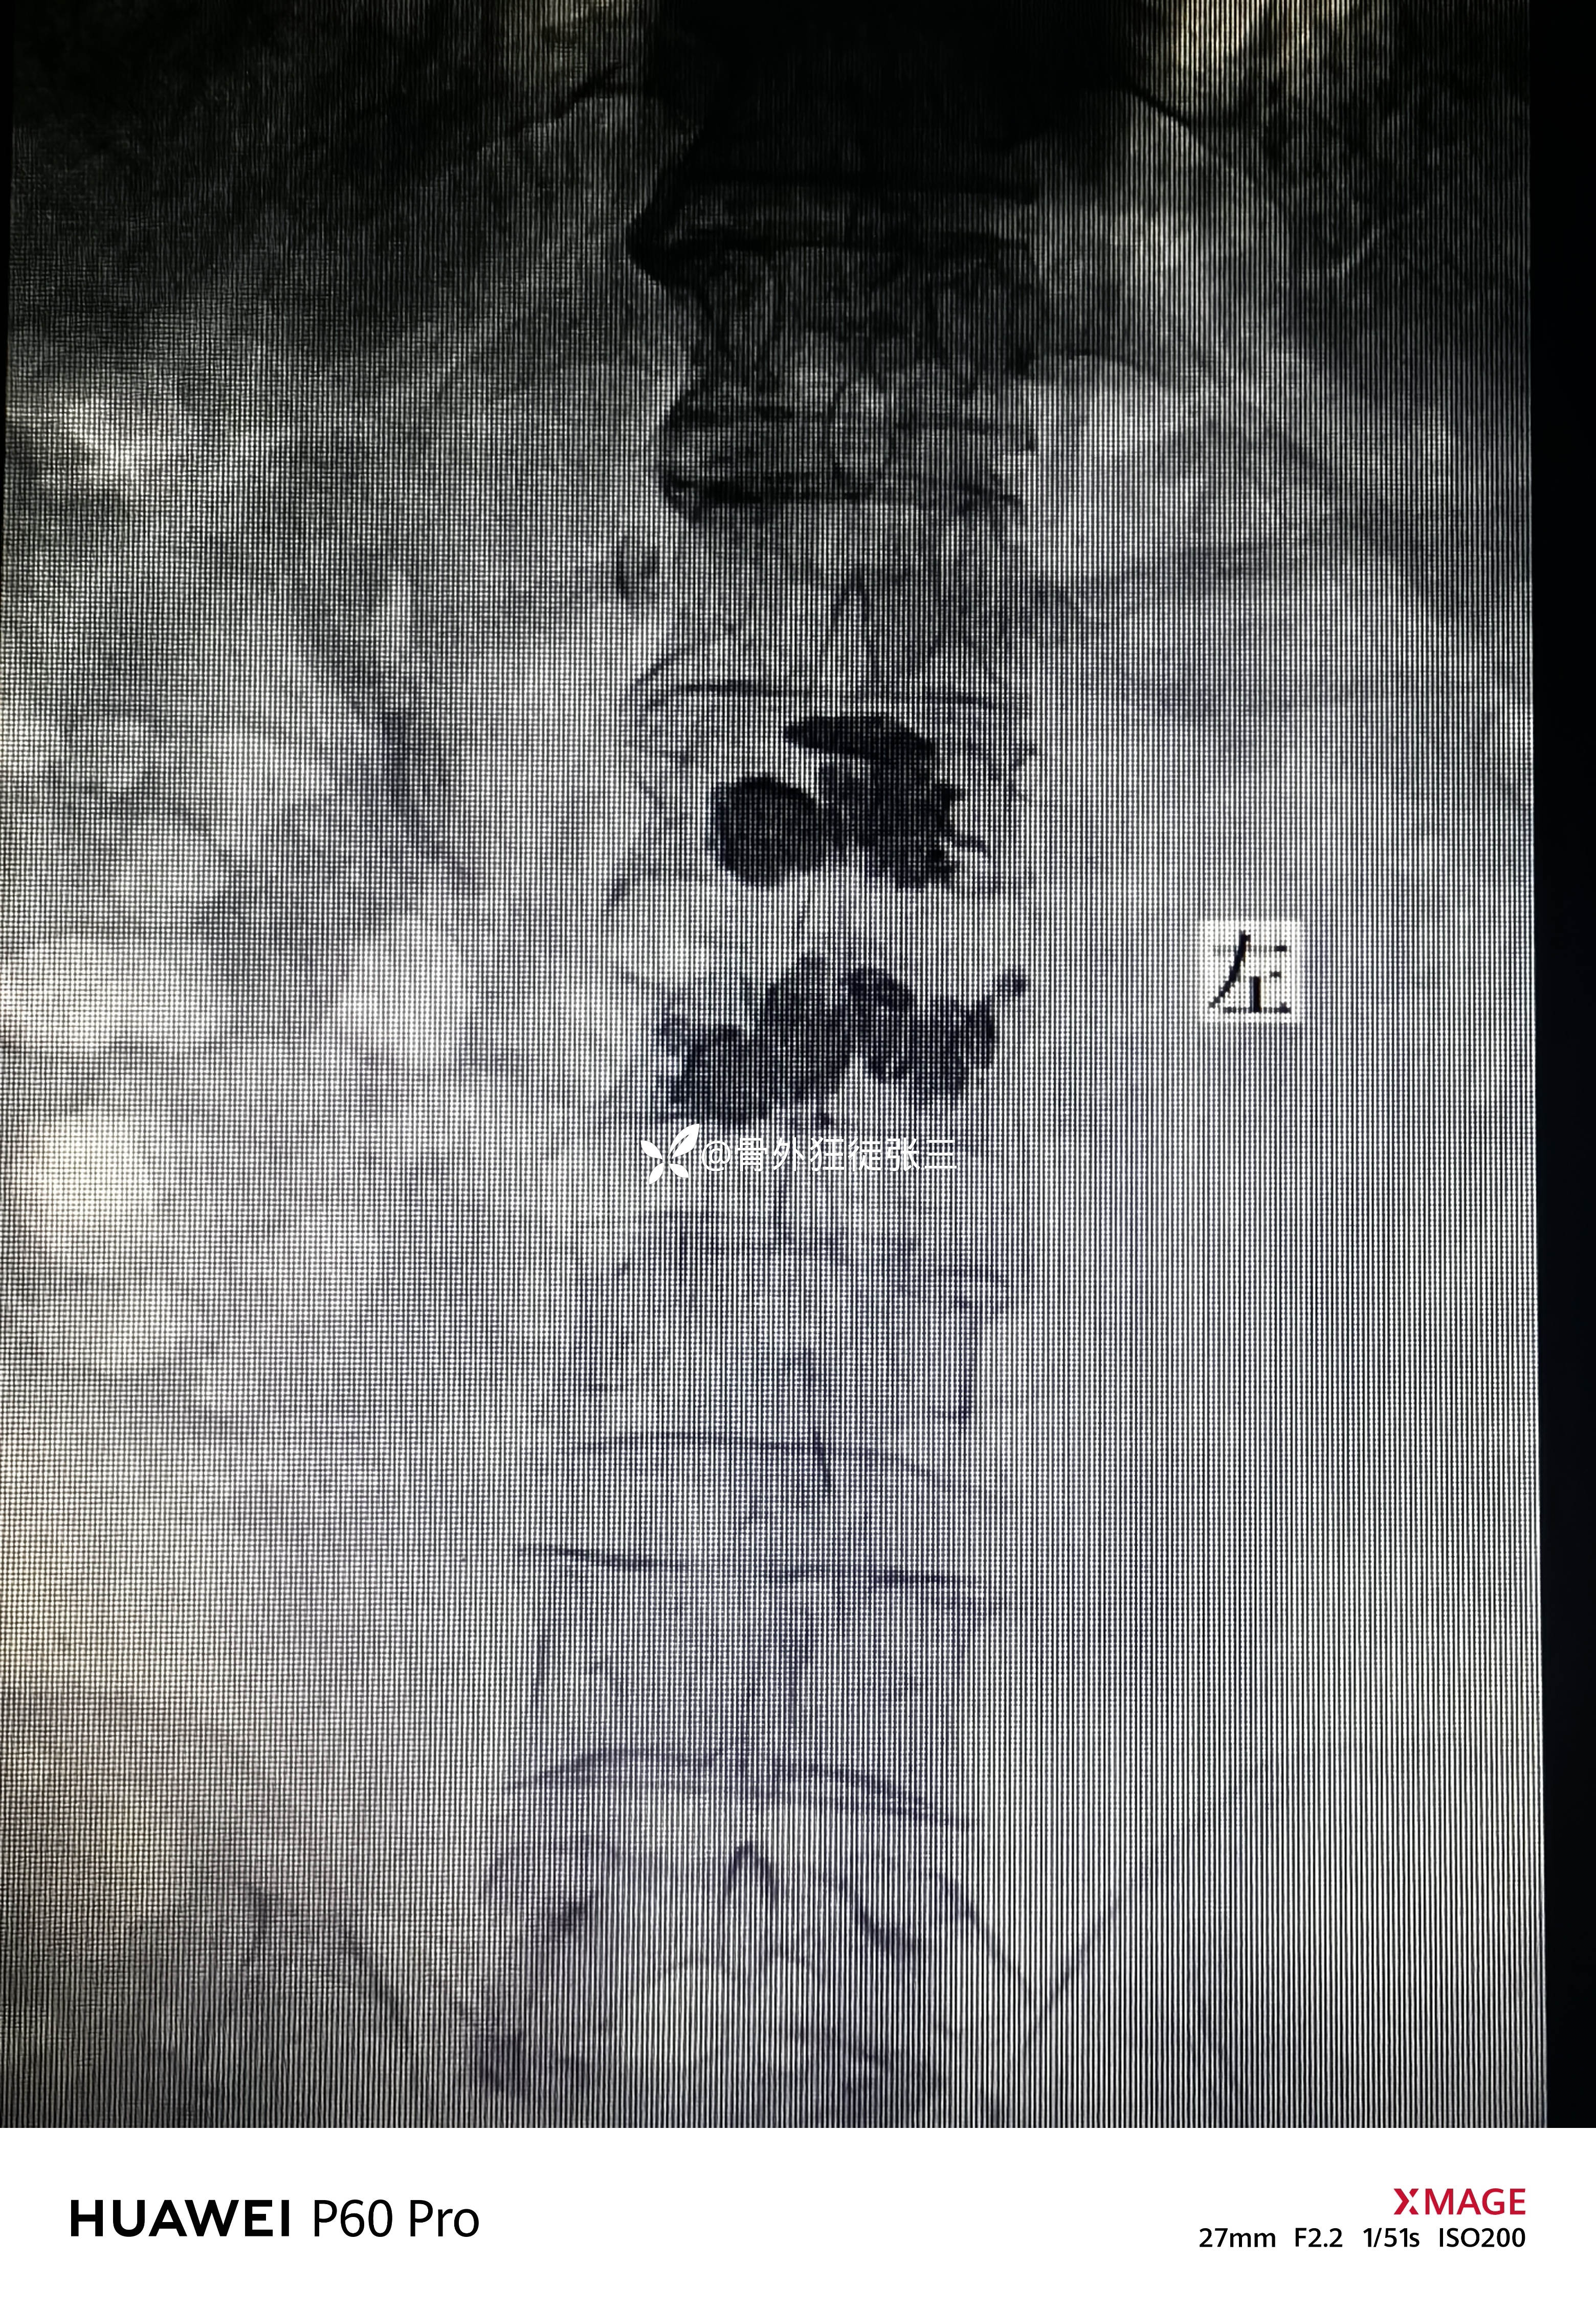

术后正位